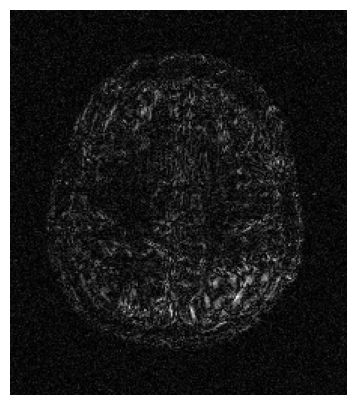

Qualitative.

The visual inspection of the images reconstructed (available in Fig. 2) at acceleration factor 4 shows little to no visible difference with the ground truth original image. However, when increasing the acceleration factor to 8, we can see that smoothing starts to appear which leads to a loss of structure as can be seen in Fig. 3.

| T1 PSNR: 38.57 SSIM: 0.9348 | T2 PSNR: 37.41 SSIM: 0.9404 | FLAIR PSNR: 36.81 SSIM: 0.9086 | T1POST PSNR: 38.90 SSIM: 0.9517 |